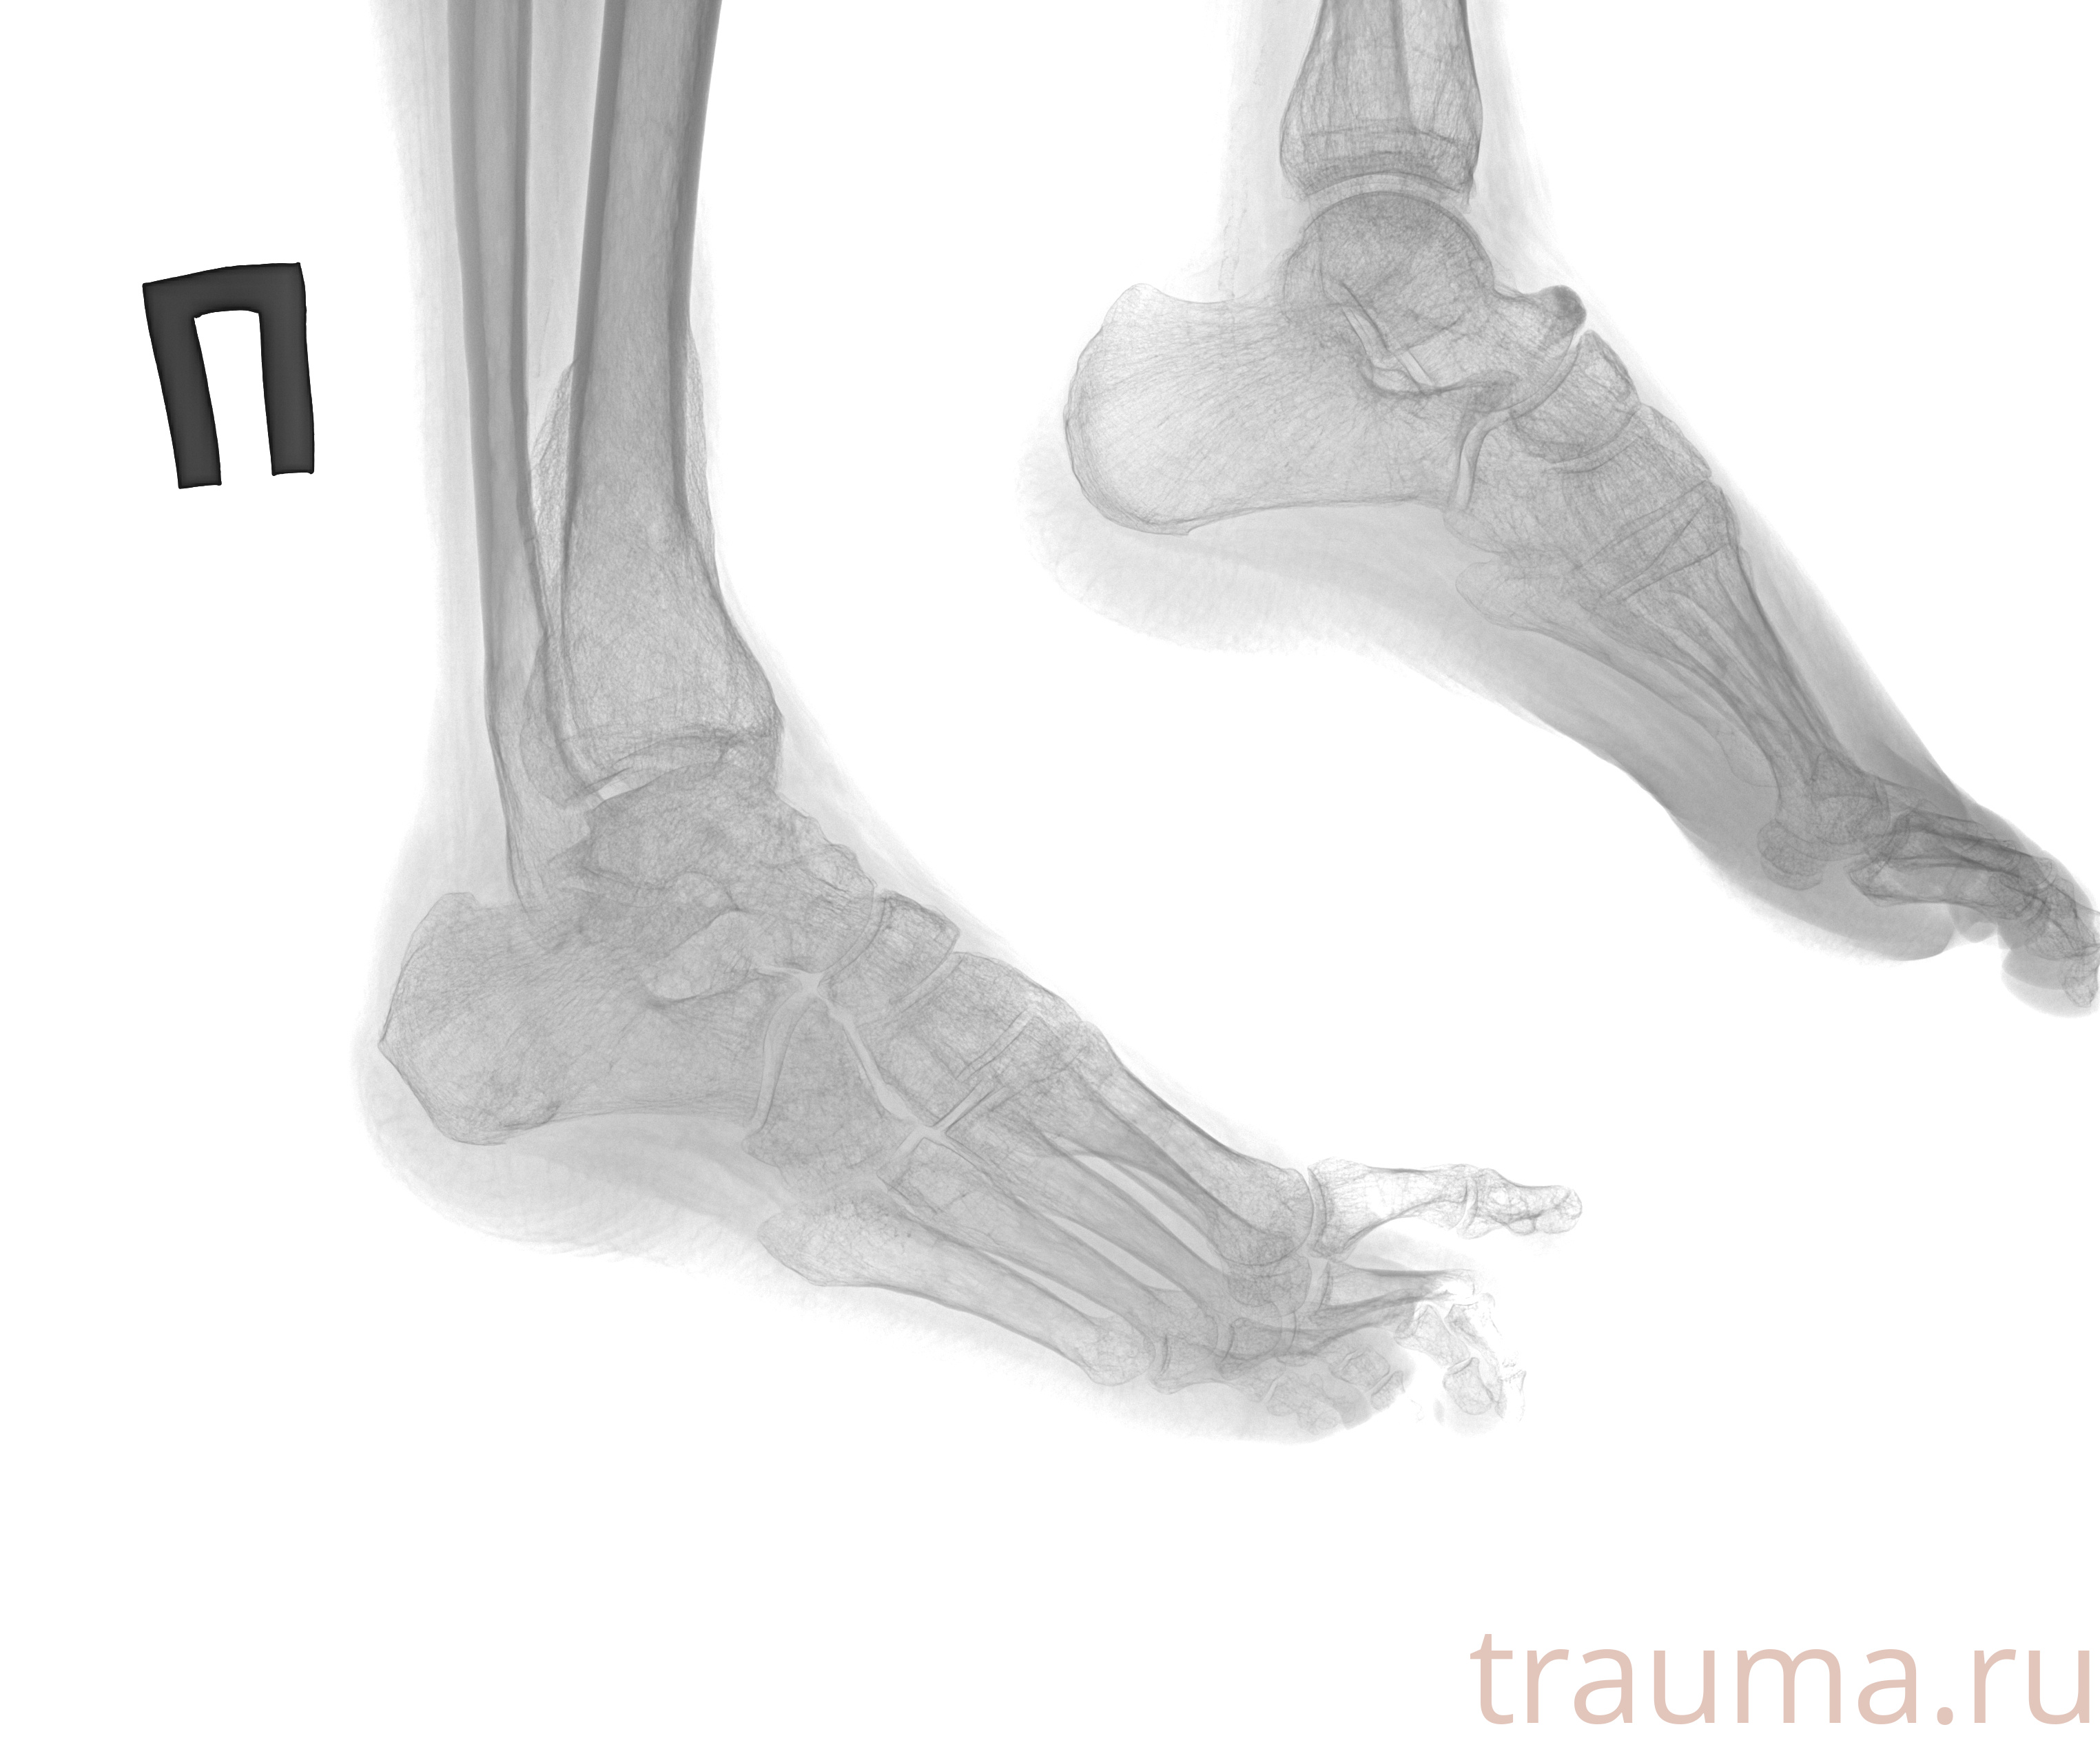

Рентген на дому: по вашему адресу приезжает врач-рентгенолог, травматолог-ортопед с мобильным рентгеновским аппаратом, проводит диагностику травмы или заболевания, делает необходимые рентгенограммы, дает рекомендации по дальнейшему лечению. Получить качественные снимки в домашних условиях возможно благодаря уникальной методике, разработанной МосРентген Центром для института  Склифосовского